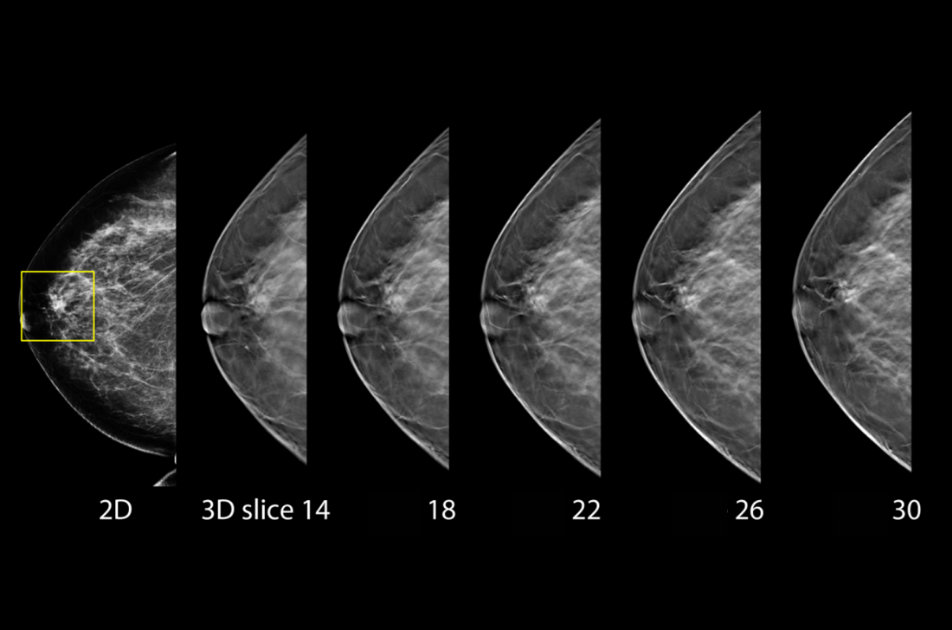

Mamografický digitální systém Hologic Selenia Dimensions je nejmodernějším mamografickým přístrojem současnosti. „Uvolňuje jen minimální dávku záření a dokáže se přizpůsobit tvaru prsu, tudíž je vyšetření pro ženy mnohem komfortnější a ohleduplnější. Pro přesnější diagnostiku využívá software s umělou inteligencí, který lékařům pomáhá rozlišit podezřelou tkáň od té zdravé. A vyniká výjimečně ostrou kvalitou obrazu, a to i při trojrozměrném zobrazení,“ uvedl předseda představenstva Nemocnice Písek a vedoucí lékař nemocničního mamografického centra Jiří Holan.

Přístroj se ovládá pomocí velké dotykové obrazovky, což je pro obsluhující zdravotnický personál velmi komfortní. Systém ho celým vyšetření vede, což snižuje případnou chybovost. Technologie umožňuje dosáhnout vysokého rozlišení i při 3D zobrazení. K analýze a hodnocení mamografických snímků slouží pracovní stanice, která má ještě jeden monitor pro zobrazování jiných snímků, například ultrazvukových.